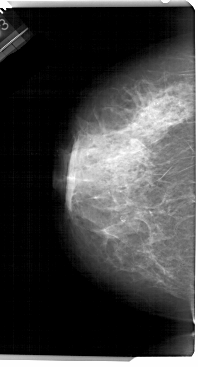

A_1305_1.LEFT_CC

LEFT_CC LINES 5491 PIXELS_PER_LINE 2956 BITS_PER_PIXEL 12 RESOLUTION 43.5 NON_OVERLAY